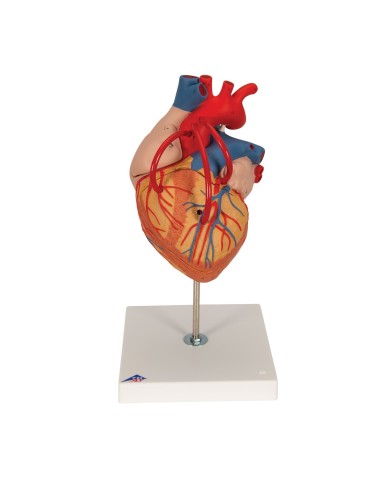

Modello anatomico di cuore, ingrandito 2 volte, su cavalletto

Questo modello dettagliato mostra, oltre alle strutture anatomiche del cuore, anche una parte del diaframma (base)